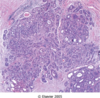

What is this an image of?

Normal breast: Ducts lined by double layer of epithelial cells and surrounded by layer of myoepithelial cells